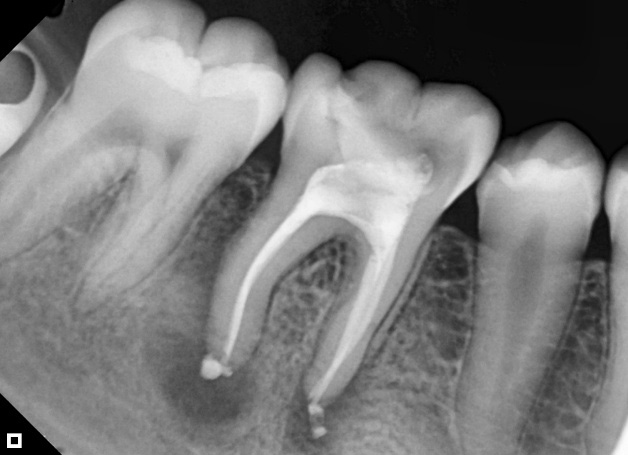

Following the filling of the canals, the pulp chamber was sealed and filled with calcium phosphate and glass ionomer cement. A follow-up appointment was scheduled after 30 and 90 days. (Figure 4A and 4B).

Figure 4: Follow-up with 30 days (A)

Figure 4: Follow-up with 90 days (B)